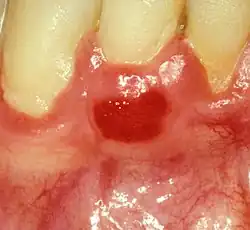

| Plasma cell gingivitis in an adult (histologically verified). |

Plasma cell gingivitis[1][2] is a rare condition,[3] appearing as generalized erythema (redness) and edema (swelling) of the attached gingiva, occasionally accompanied by cheilitis (lip swelling) or glossitis (tongue swelling).[4] It is called plasma cell gingivitis where the gingiva (gums) are involved,[5] plasma cell cheilitis,[5] where the lips are involved, and other terms such as plasma cell orifacial mucositis,[5] or plasma cell gingivostomatitis where several sites in the mouth are involved. On the lips, the condition appears as sharply outlined, infiltrated, dark red plaque with a lacquer-like glazing of the surface of the involved oral area.[5]

Plasma cell gingivitis appears as mild gingival enlargement and may extend from the free marginal gingiva on to the attached gingiva.[6] Sometimes it is blended with a marginal, plaque induced gingivitis, or it does not involve the free marginal gingiva. It may also be found as a solitude red area within the attached gingiva (pictures). In some cases the healing of a plaque-induced gingivitis or a periodontitis resolves a plasma cell gingivitis situated a few mm from the earlier plaque-infected marginal gingiva. In case of one or few solitary areas of plasma cell gingivitis, no symptoms are reported from the patient. Most often solitary entities are therefore found by the dentist.[2]

The gums are red, friable, or sometimes granular, and sometimes bleed easily if traumatised.[6] The normal stippling is lost.[7] There is not usually any loss of periodontal attachment.[6] In a few cases a sore mouth can develop, and if so pain is sometimes made worse by toothpastes, or hot or spicy food.[7] The lesions can extend to involve the palate.[7]